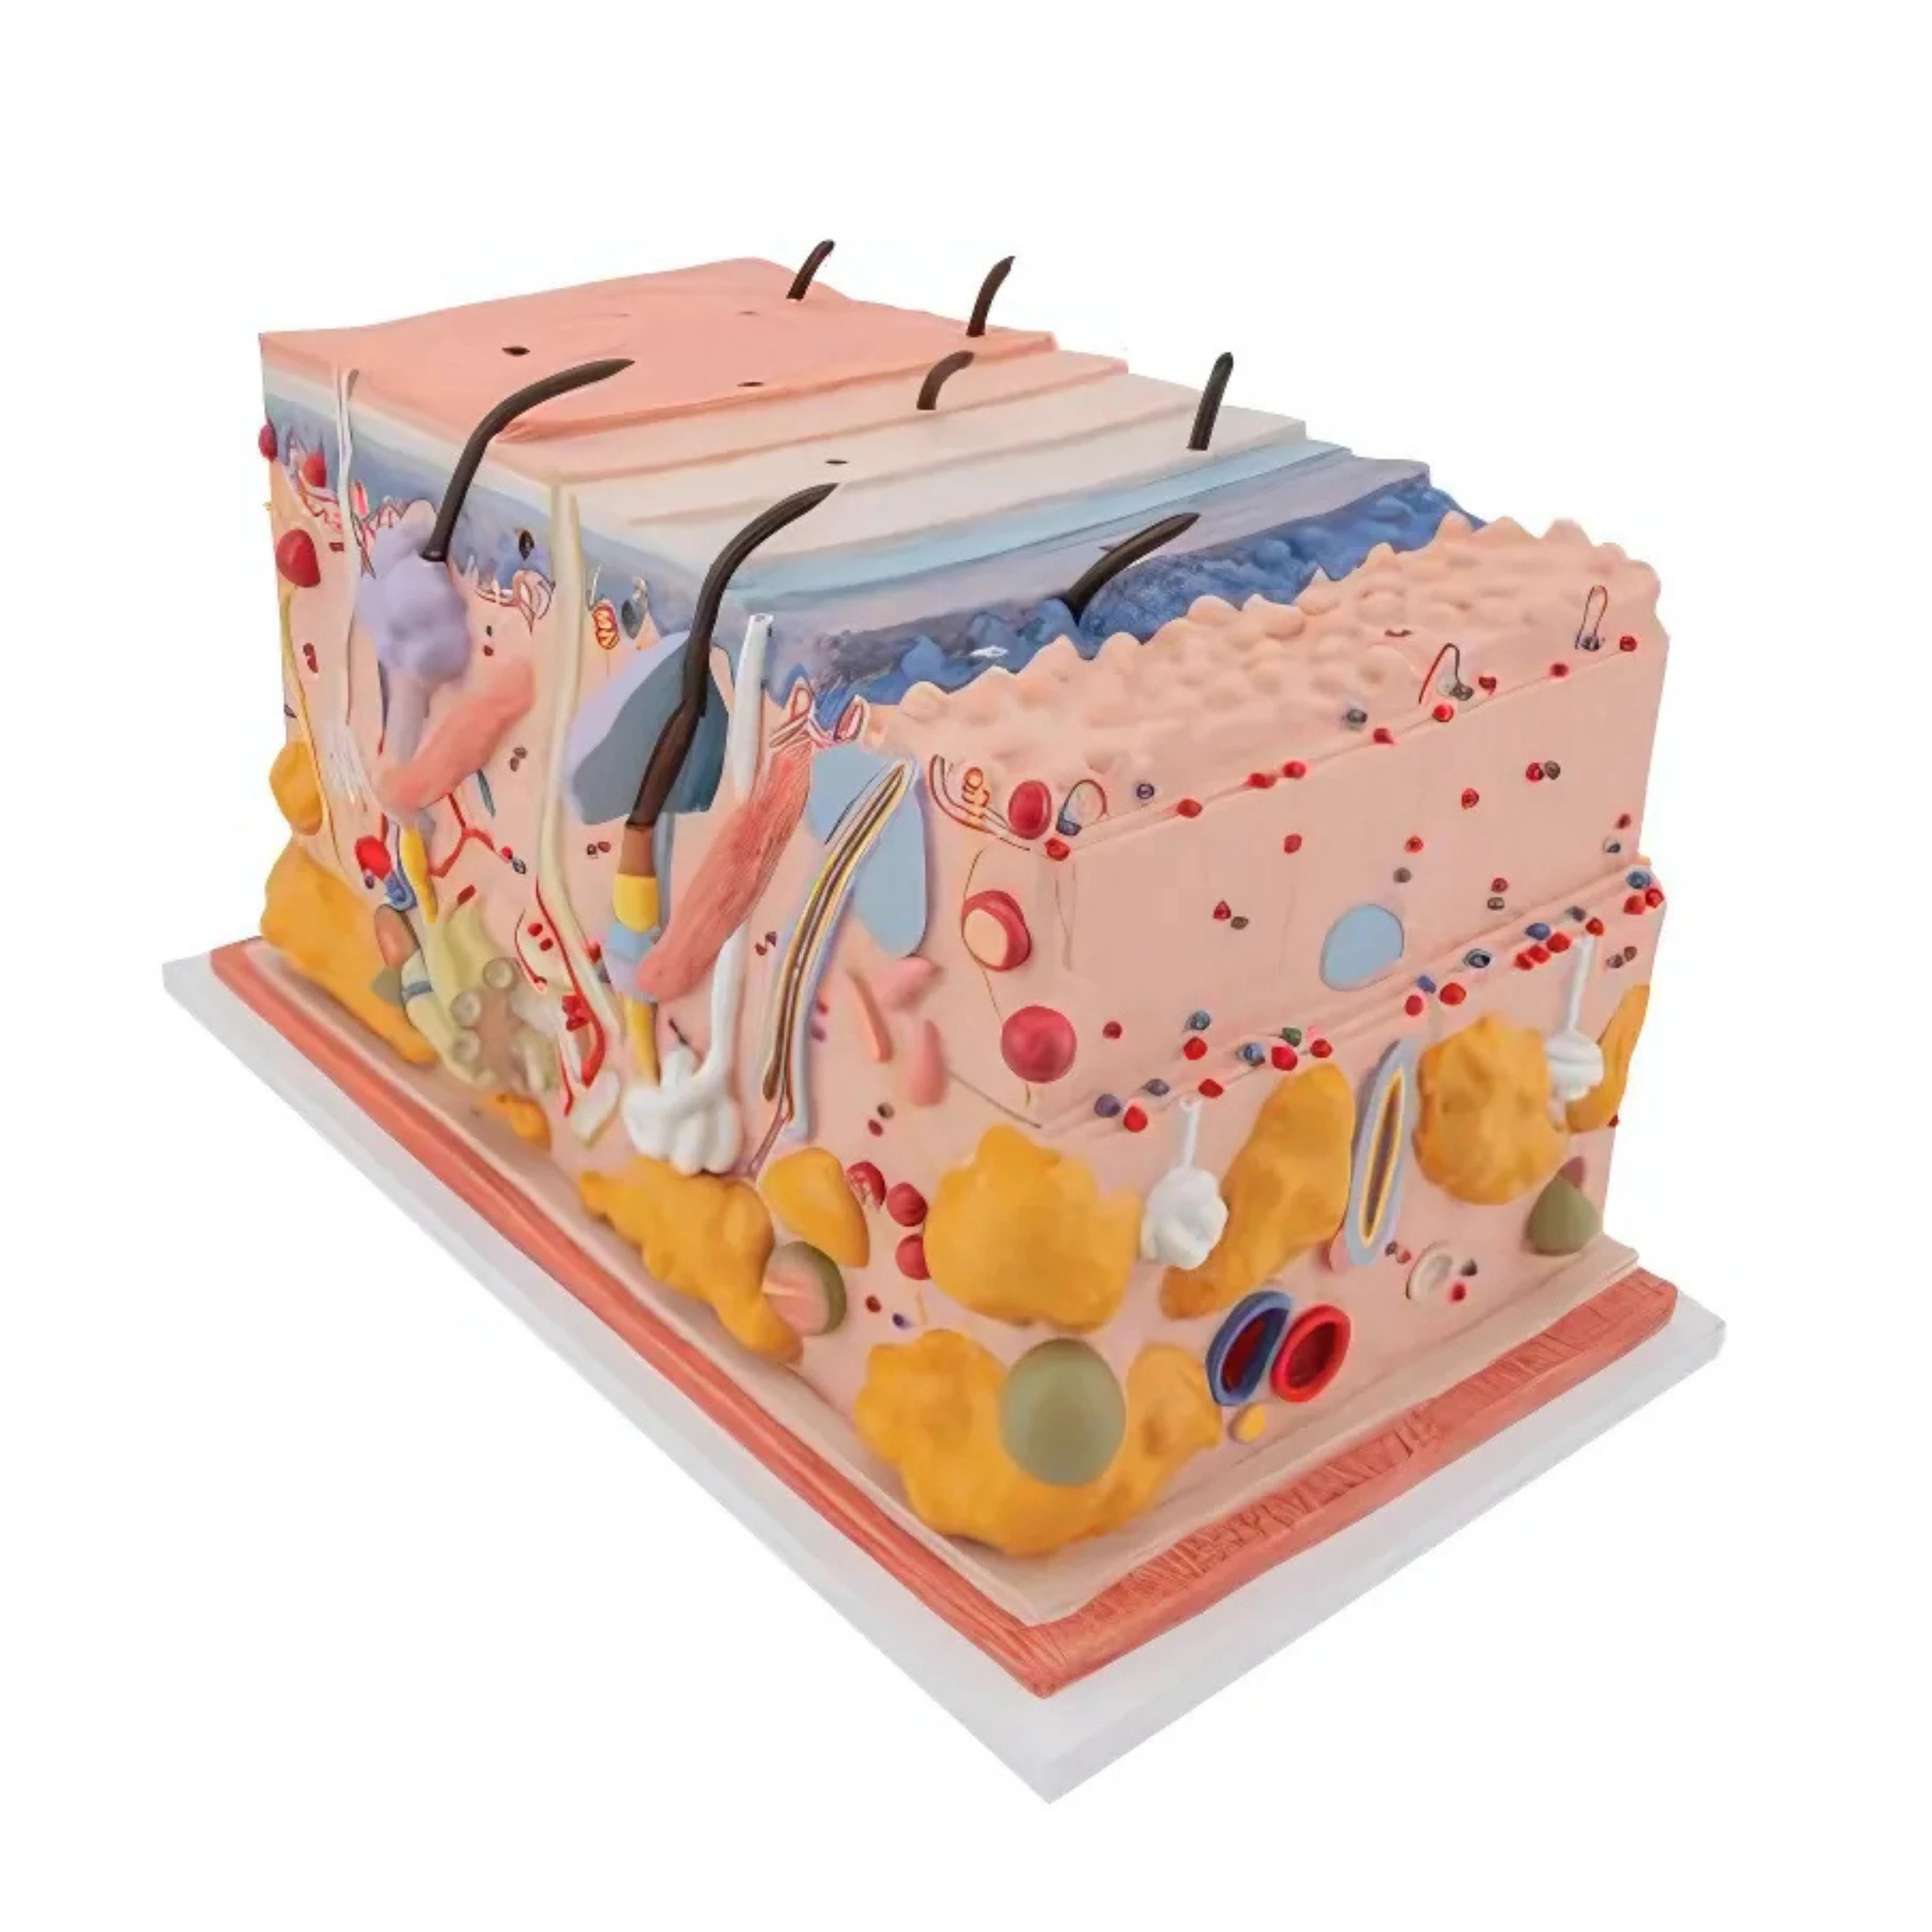

La piel, modelo en bloque, 70 veces su tamaño natural - 3B Smart Anatomy

Precio de venta$15,519.81